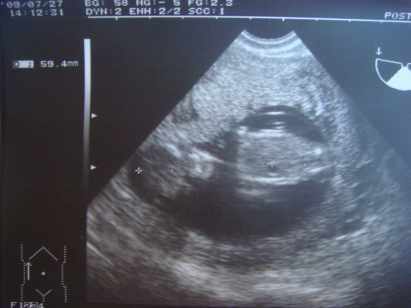

Pocimaci CRL 59,4mm hosszú, BPD 21mm, combcsont 9mm :lol: és a lényeg: NT 1,1mm.

Szóval minden a legnagyobb rendben. Méretei szerint akár egy héttel idősebb is lehet. Luca 12+6naposan volt CRL 60mm.

Megint riszált, szóval ajánlom, hogy lány legyen! :lol:

Jól átbogarásztuk a gerincét, kezeit, lábait. Tetőtől talpig megkukkoltuk!

Legközelebb aug. 24-én megyek az AFP miatt.

Meg most a héten, csütörtökön veszik le a vért a kombi teszthez!

Na a képek (a második babafotól látjátok, hogy összeüti az apró lábait. Kb fél cm lehet, vagy annyi sem egy tappancs):